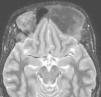

El estudio de resonancia magnética (RM) cerebral evidencia una lesión endomedular, frontoetmoidal izquierda, insuflante, hipointensa, que produce discreto efecto de masa sobre los surcos corticales frontobasales izquierdos (figs. 1 y 2). Para mejor visualización de partes óseas se realiza tomografía computarizada de cráneo y órbitas que muestra como la afectación ósea frontoetmoidal izquierda alcanza el techo de la órbita. La lesión es expansiva, mixta, esclerótica-lítica, y con una atenuación característica en «vidrio deslustrado o cristal esmerilado» (fig. 3). La imagen radiológica sugiere una displasia fibrosa craneofacial. El estudio oftalmológico mostró una agudeza visual y campimetría normales. La serie ósea descartó afectación a otros niveles. Se han realizado controles de RM sin encontrarse progresión tras dos años de seguimiento.